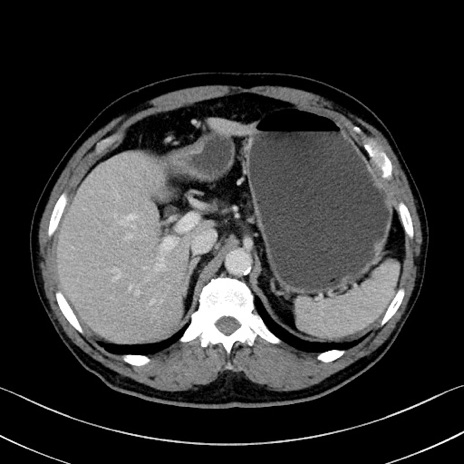

症例35(横断像)

【症例】70歳代 男性

【主訴】腹部膨満、嘔吐

【現病歴】昨日より腹部膨満感出現。本日増悪し、仙痛出現。嘔吐あり、受診。

【既往歴】糖尿病、胆摘後

【身体所見】BP 149/80mmHg、HR 74/min、BT 35.9℃、腹部:膨満、軟、圧痛なし。腸雑音減弱あり。上腹部正中切開瘢痕あり。

【データ】WBC 13500、CRP 1.72